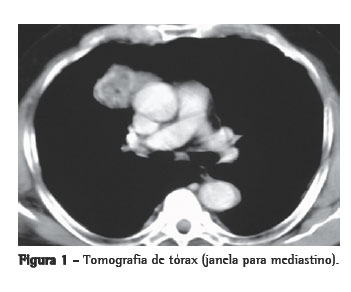

Relato de casoPaciente de 66 anos, do sexo masculino, natural de São Luiz (MA) e procedente de São Paulo, sem antecedentes mórbidos e sem história de tabagismo, foi admitido no ambulatório sem queixas e em bom estado geral. Trazia exame radiológico, realizado em outro serviço há dez anos, revelando a presença de tumor de mediastino anterior, com cerca de 4 cm de diâmetro. A investigação prosseguiu com a realização de uma nova radiografia e uma nova tomografia computadorizada de tórax, as quais revelaram um tumor de contornos espiculados, medindo 3,0 × 4,0 cm, localizado no mediastino anterior à direita e com as mesmas características encontradas nos exames realizados anteriormente (Figura 1). Apresentava exames laboratoriais e prova de função pulmonar normais. Os marcadores tumorais estavam normais. Foi confirmado o diagnóstico sindrômico de tumor de mediastino anterior, e indicado tratamento operatório.